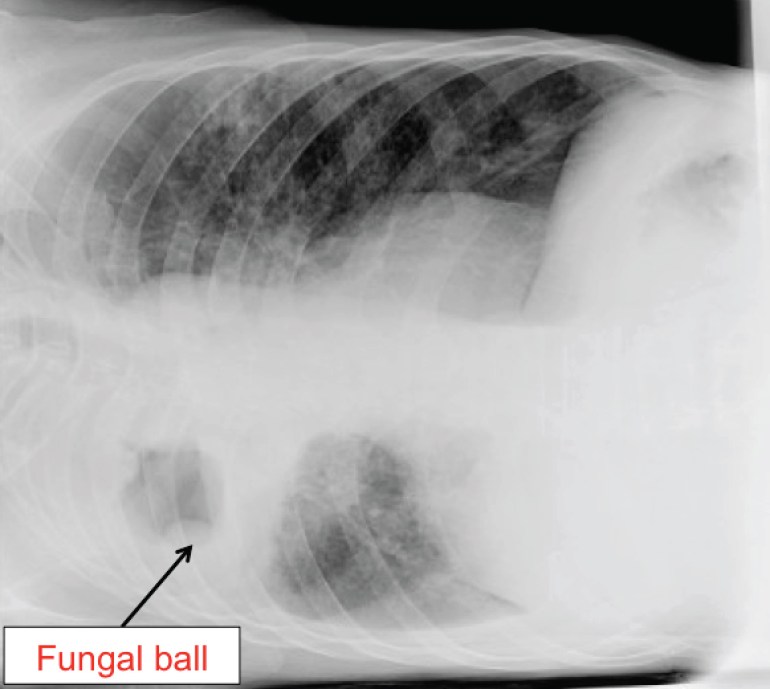

The classical way to make the diagnosis is to have the chest X-ray taken with the patient in a different position, as fungal balls are generally mobile and will shift its position according to gravity. Here (below) is an image of the same patient lying in the right lateral recumbent position.

Chest X-ray with patient in the right lateral recumbent position. The fungal ball has “fallen” by gravity.